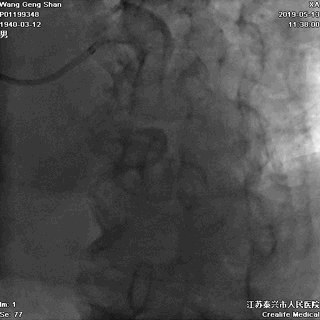

LCX球囊拘禁,主支支架释放

回撤LCX球囊

支架球囊再次扩张支架